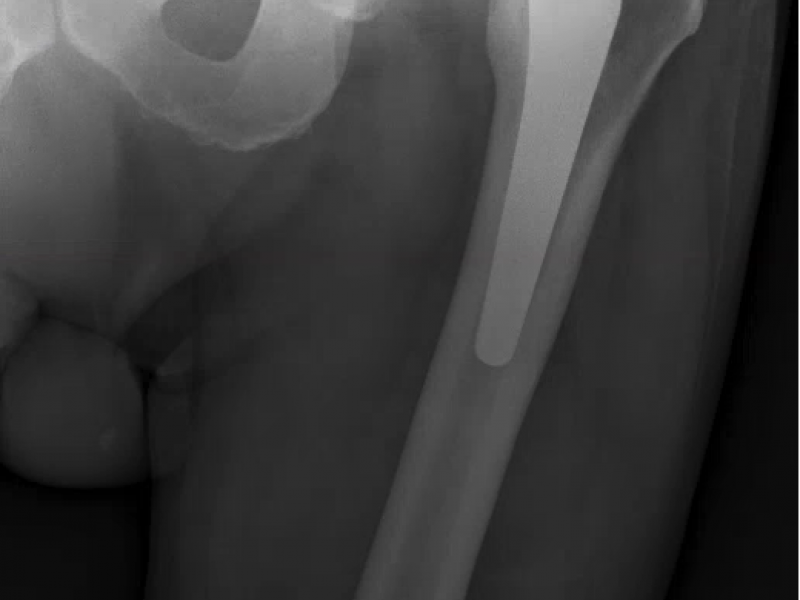

A 62 yo male with a hx of bilateral hip replacements c/o, "I